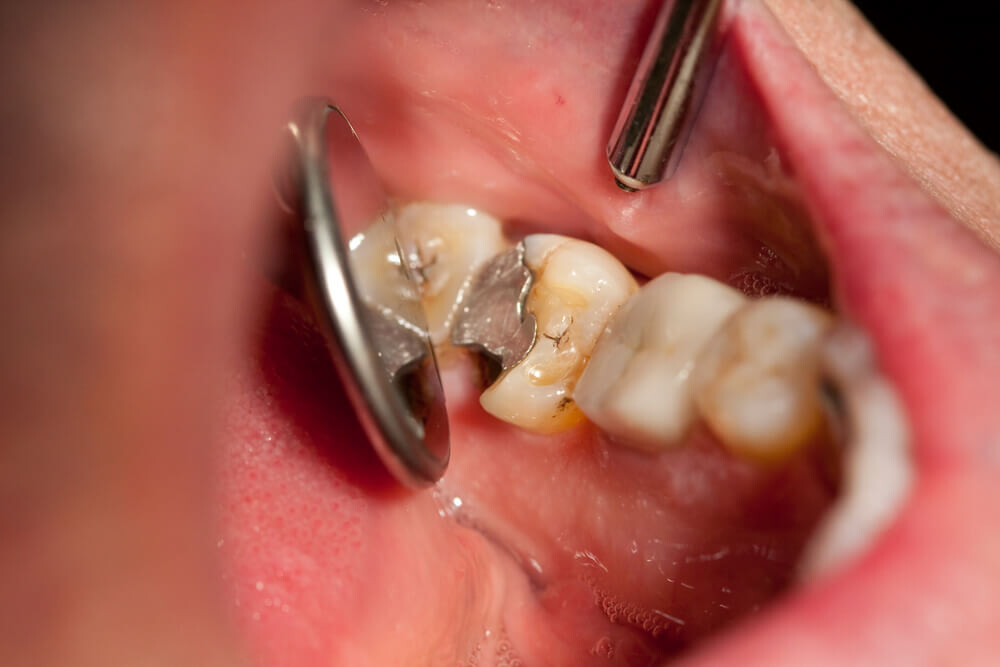

Tooth decay

As tooth decay progresses, it can reach the softer inner layers of the tooth, called dentin and pulp, resulting in sensitivity to hot, cold, or sweet foods and drinks and eventually leading to a toothache. If left untreated, tooth decay can result in an abscess, a painful infection at the root of the tooth that can cause severe pain and swelling. Adhering to your routine dental check-ups, practicing good oral hygiene, and eating a healthy diet can help prevent tooth decay and the resulting toothache.

Abscessed tooth

An abscessed tooth occurs when the pulp inside your tooth becomes infected, typically due to decay or damage. The infection can spread to the tooth’s root and surrounding tissues, causing pain and swelling. In some cases, a pocket of pus may form in the affected area, leading to additional discomfort and even fever. Abscessed teeth may also cause sensitivity to hot or cold foods, a bad taste in your mouth, and difficulty chewing or speaking. If you have an abscessed tooth, inform your provider to prevent further complications and potential tooth loss.